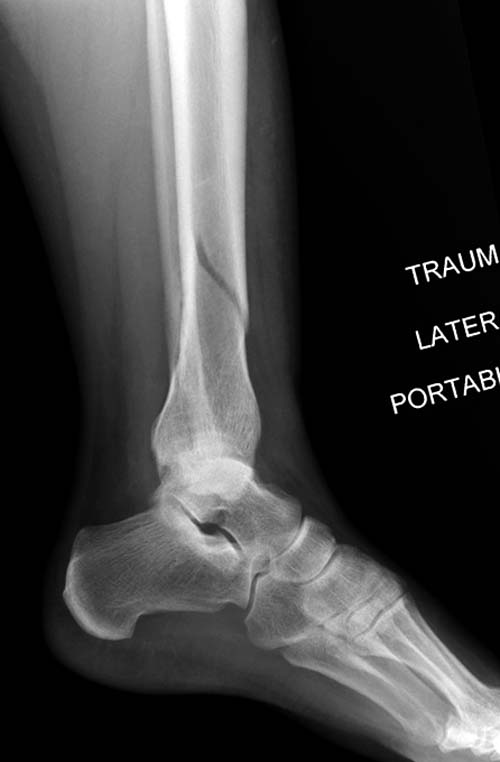

Первый случай, где перелом в результате падения с  небольшой высоты, где

мортиз рентген снимок показал отстутствие укорочения наружной

лодыжки и КТ срезы подсказали направления атаки. После такой фиксации

нет надобности в гипсовой повязке, брейс и через две недели движения в

суставе без нагрузки.